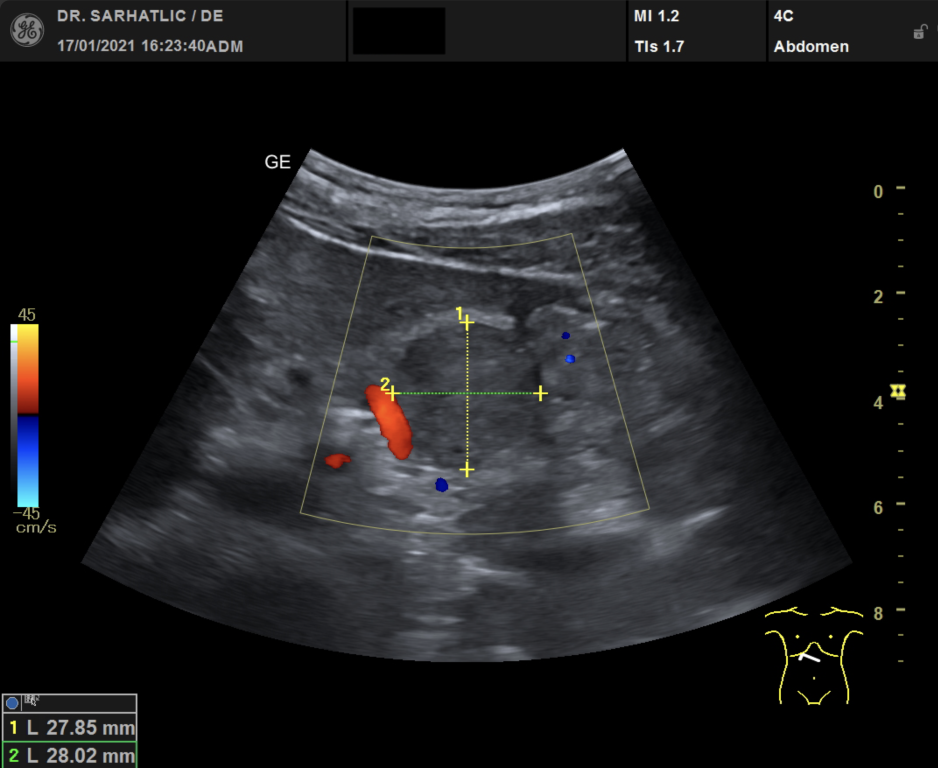

MODERNE ULTRASCHALLDIAGNOSTIK- Modernes Farbdoppler-Ultraschallgerät

- Hochauflösende Schallköpfe

- Detaillierte Organuntersuchungen

- Ultraschall aller inneren Organe (z. B. Leber, Bauchspeicheldrüse, Nieren, Prostata, Schilddrüse)

- Ultraschall der Gefäße (z. B. Halsschlagadern)